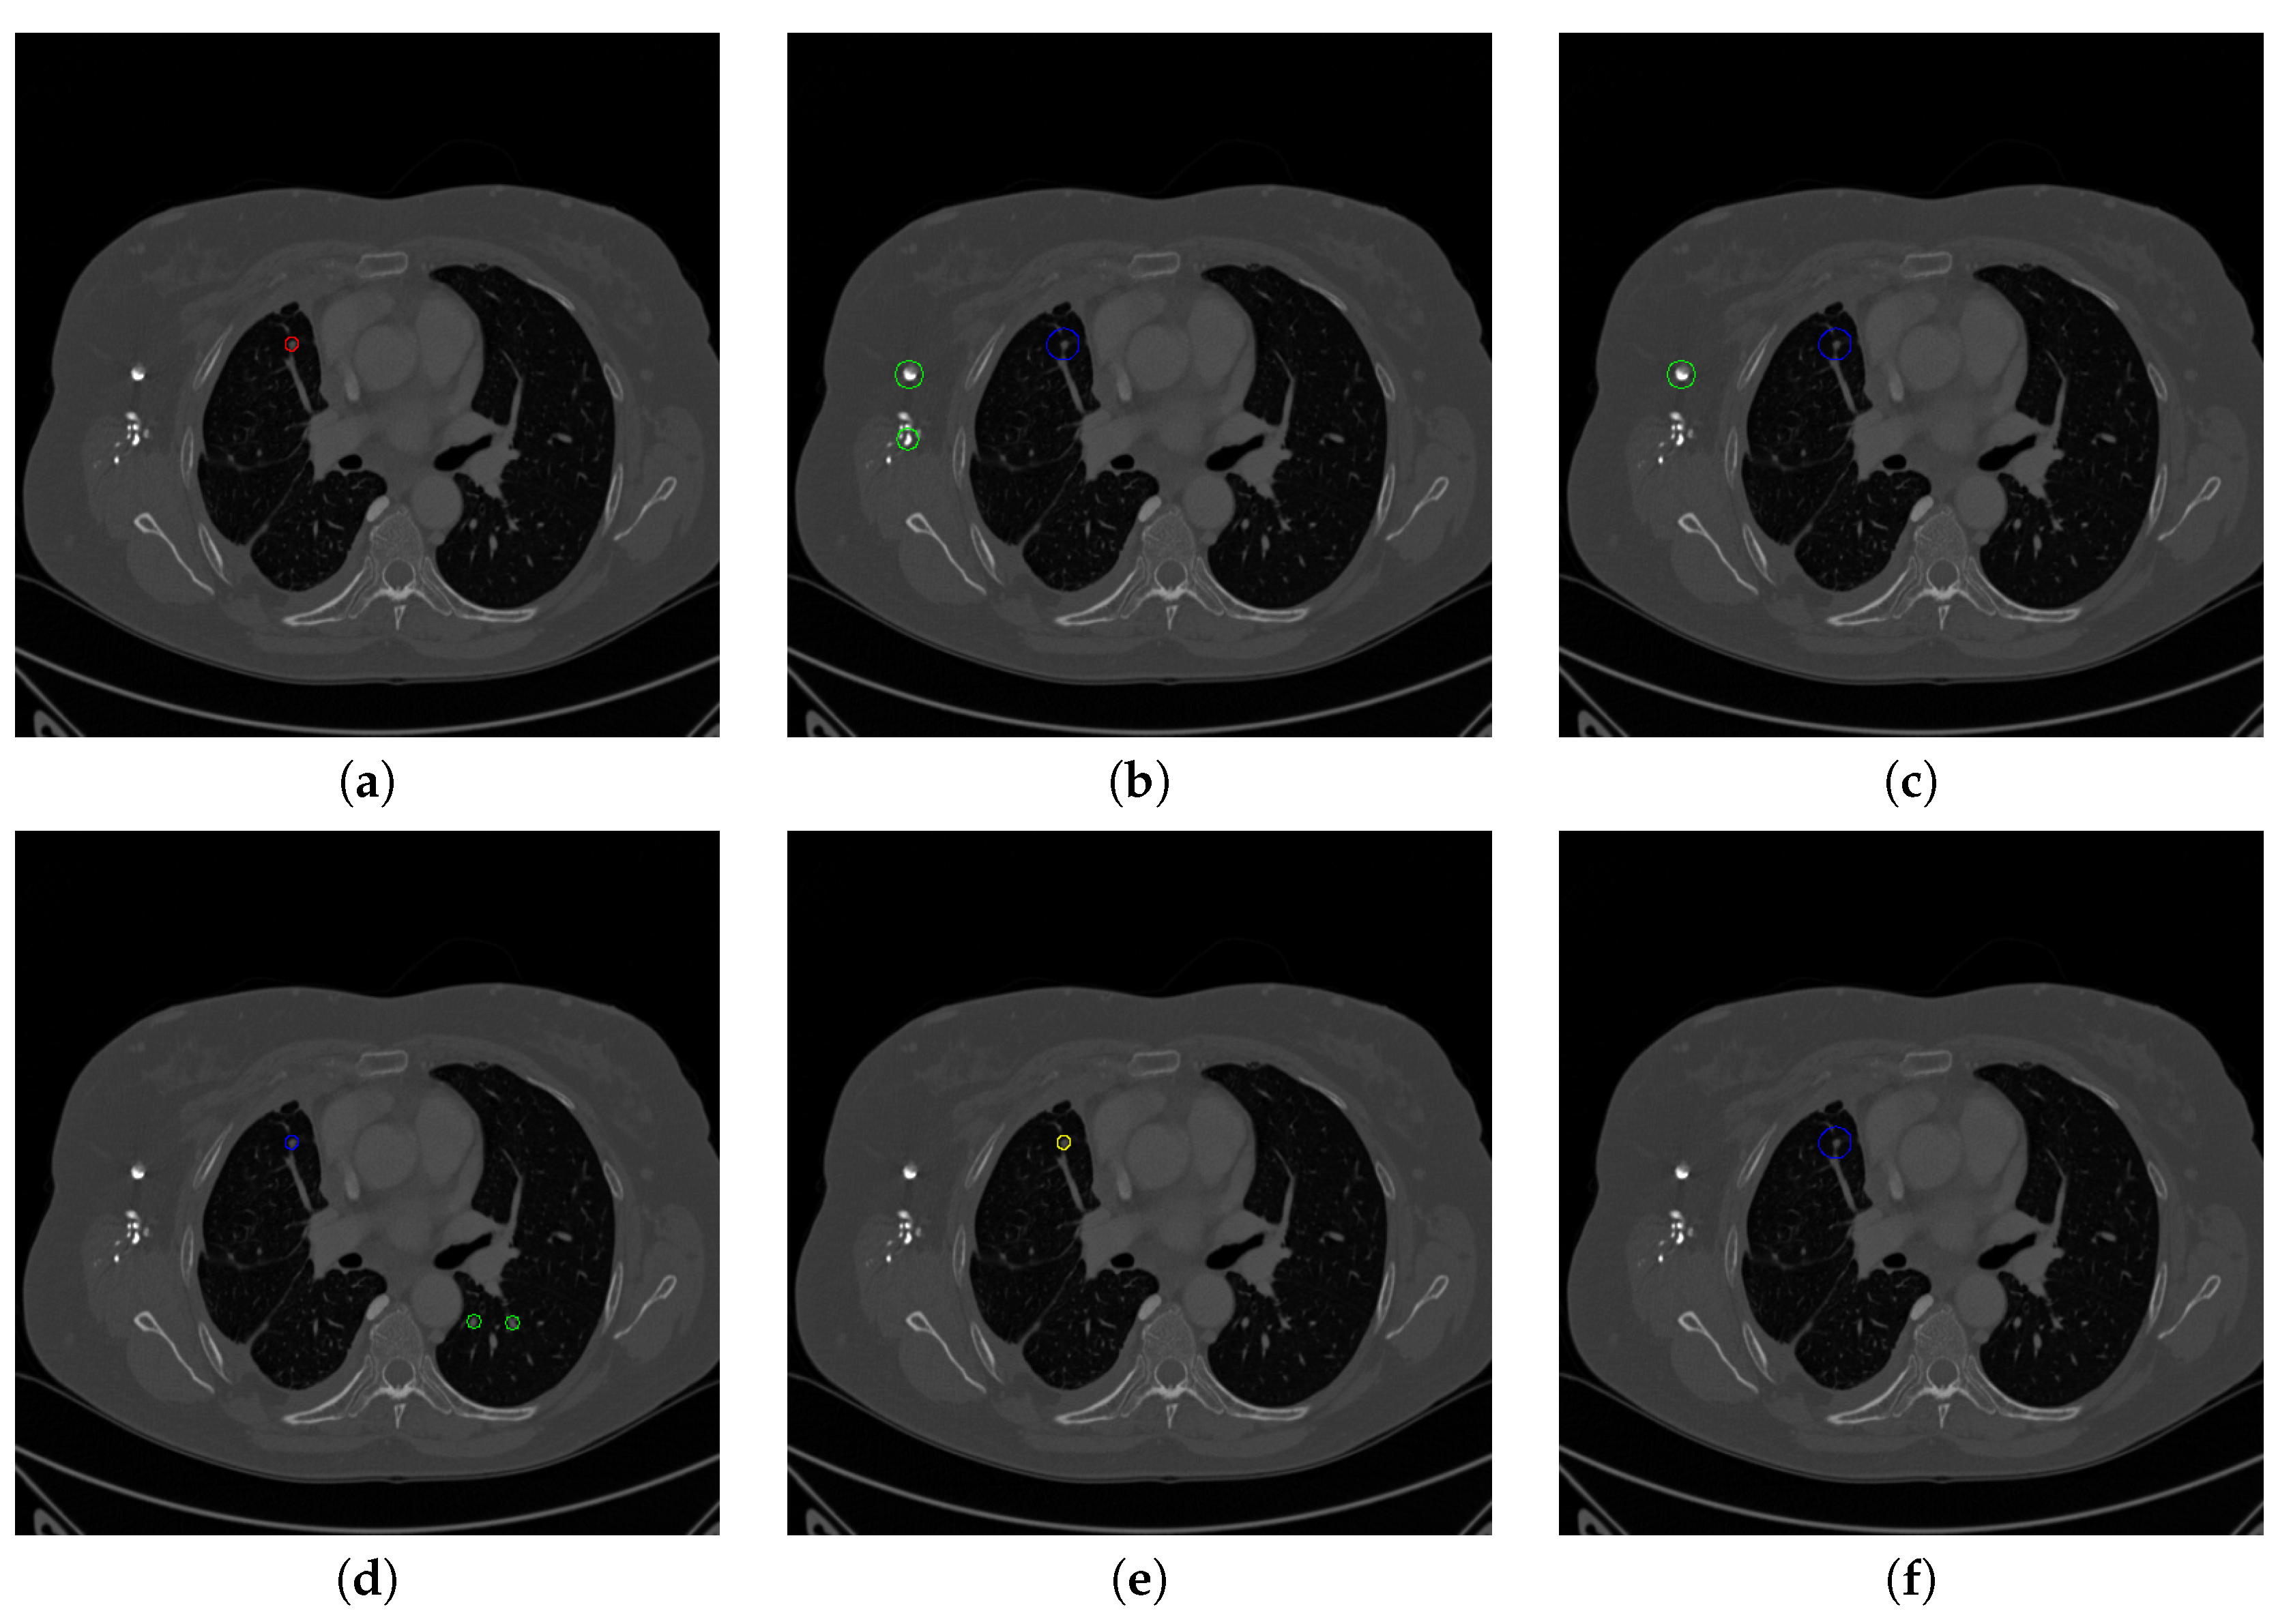

Figure 17. The result of detecting pulmonary nodules by different methods on one example image in LUNA16 dataset. Red circle represents the ground truth region of nodules, blue circles represent the correct estimation of pulmonary nodules, green circles represent the over-detected nodules, while yellow circles denote the nodules being omitted. (ai) are: ground truth nodule in the given chest CT image, nodule detected by 3D-FCN, MR-CNN, 3D-UNET, PRN-HSN, DCNN, CLAHE-SVM, MASK-RCNN and our proposed method.

Figure 18. The result of detecting pulmonary nodules by different methods on another example image in LUNA16 dataset. Red circle represents the ground truth region of nodules, blue circles represent the correct estimation of pulmonary nodules, green circles represent the over-detected nodules, while yellow circles denote the nodules being omitted. (ai) are: ground truth nodule in the given chest CT image, nodule detected by 3D-FCN, MR-CNN, 3D-UNET, PRN-HSN, DCNN, CLAHE-SVM, MASK-RCNN and our proposed method.

Figure 17 and Figure 18 illustrates the performance of pulmonary nodule detection by different methods on two example images in the LUNA16 dataset. In addition, Figure 19 and Figure 20 illustrates the performance of pulmonary nodule detection by different methods on two examples images in the TianChi dataset. As marked by green circles in Figure 18b,c and Figure 19c, the 3D-FCN and MR-CNN directly detected the nodule candidates from the original CT image without pre-processing, resulting in the incorrect determination of non-nodule tissue outside lung as nodule since the outside-lung organs are not filtered out from the nodule candidates. The 3D-UNET and PRN-HSN add the lung parenchyma region segmentation stage before detecting the nodule candidates inside-lung, so they provide better performance than 3D-FCN and MR-CNN in decreasing the over-estimation rate. However, they still suffer from unsatisfactory results for the following reasons: (1) the lung parenchyma segmentation is generated by simple thresholding with morphological operations so the near-edge regions are lost, shown as the one marked by yellow circle in Figure 20d,e; (2) the convolution kernel used in nodule candidate detection of 3D-UNET is with a small receptive field to learn global features from the image, so it is likely to confuse some small tissues as true nodules with small sizes, shown as the one marked by green circle in Figure 18d and Figure 20d; and (3) the proposed hierarchical saliency network (HSN) in PRN-HSN for nodule candidate classification omits the information with different resolutions, resulting in that the small-size nodule within the weakened, low-resolution region cannot be correctly recognized, as shown by the yellow circle in Figure 18e. The DCNN method simply applies the Faster RCNN method to provide good performance with low computational cost, but it may omit the nodules on the parenchymal edge shown as yellow circles in Figure 20f. CLAHE-SVM method adds a contrast-enhancement pre-processing before the nodule detection, leads to better performance on detecting nodules in the low-contrast region. However, it is easily to over-enhance the small-size tissues and over-estimate them as nodules, as shown by the green circles in Figure 19g andFigure 20g. The detection is also implemented over the whole image, so the nodule on the parenchyma edge may be under-estimated show by the yellow circle in Figure 20g. The Mask-RCNN method provides better effects than the above methods because of the good performance of Mask-RCNN in object detection. However, the performance is not stable for the small-size tissues and the irregular-shape nodule, shown by the green circles in Figure 17h and Figure 19h, and the yellow circle in Figure 19h. The proposed method takes the advantage of a series of U-Net-like networks to perform the nodule detection following a “coarse-to-fine” order of inside-lung region detection, nodule candidate detection and nodule determination. The U-Net network is modified by embedding inception structure, replacing the convolution and pooling by dilated convolution, and adapting multi-scale pooling and multi-resolution convolution connection, for different requirements of the three stages, respectively. Moreover, it makes use of the MSE loss, VGG-19-based perceptual loss as the complement of dice loss to optimize the whole framework. Therefore, as shown in Figure 17i, Figure 18i, Figure 19i and Figure 20i, the proposed framework provides superior performance on pulmonary nodule detection with low over-estimation of non-nodule tissues at the same time.